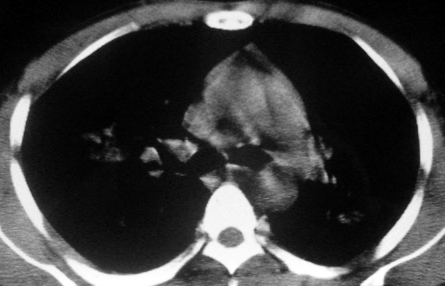

男,36岁,一月前醉酒淋雨后发热咳嗽,气短进行性加重.

抗生素治疗无效,痰检(一).

影像诊断:结核? 还有其他考虑吗?

双肺内中部见略不对称性蝶翼状高密度区,边界不清,部分呈磨玻璃样密度,并可见含气支气管征。肺门、纵隔内未见肿大淋巴结影。无胸腔积液。

考虑:1、肺炎,建议进一步查冷凝集试验除外支原体肺炎;

2、不除外霉菌感染。

双肺斑片状密度均匀病灶,边界模糊可见充气支气管征,上野多于下野,不支持结核,1肺内感染,2查肾功,中心型肺水肿待除外.

双肺中上野对称分布蝶翼样不均匀密度增高影,有支气管充气征,纵隔未见肿大淋巴结,发病突然,抗炎治疗无效,还是要考虑结核。

还是考虑肺水肿!蝶翼征.肺门增大,肺血管影增粗,!!病变累及中内带为主!要排外支原体感染.

支持: 双肺内中部见略不对称性蝶翼状高密度区,边界不清,部分呈磨玻璃样密度,并可见含气支气管征。肺门、纵隔内未见肿大淋巴结影。无胸腔积液。